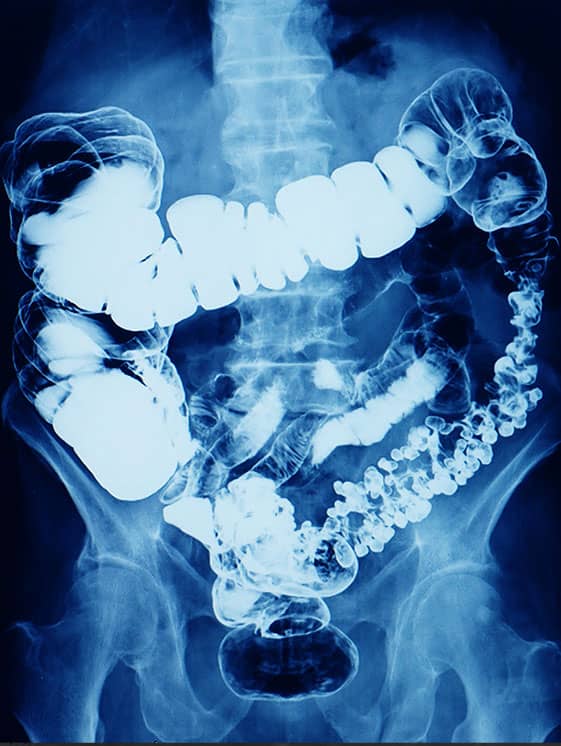

Incidência PA ou AP – Pós-evacuação: enema baritado

Enema baritado na fase de pós-evacuação.

Justificativa para realização do exame

Visualizar os padrões da mucosa do intestino grosso com resíduo de contraste para estudo de pequenos pólipos e defeitos.

Principais estruturas demonstradas

Todo o intestino grosso, com contraste residual.

Fatores técnicos e posicionamento

• DFF: 1m.

• Tamanho do filme/receptor de imagem e sentido: 35x43cm no sentido longitudinal.

• Técnica de referência: 4mAs e 100 KV, na mesa.

• RC: perpendicular no centro do filme e ao nível das cristas ilíacas.

• Posição do paciente e da parte ou região do corpo: paciente em decúbito ventral ou dorsal, com os braços para cima, fornecendo um travesseiro para o rosto, que deve ficar de lado.

• Respiração: parar a respiração e expor durante e expiração.

Atenção

A sala de exames deve promover o mínimo de conforto para o paciente, com um banheiro amplo para realizar a evacuação sem estar distante do aparelho, proporcionando comodidade.